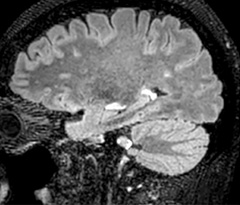

Comprehensive stroke MRI within acceptable time

Dr. Savatovsky appreciates the improvements and flexibility that Elition with Compressed SENSE and MultiBand SENSE provides, particularly for stroke patients. “For stroke, it allows us to cut about 5 minutes off of our stroke protocol, or to keep the same acquisition time and get more insights.”

The ability to perform more sequences can help in making a swift and confident diagnosis. “For example, our stroke cases usually include the regular sequences that every center does (b1000 diffusion, FLAIR, time-of-flight angiography), but we also image supra aortic vessels, and we can replace a gradient echo sequence with a fast 50-second susceptibility-weighted sequence, and all of this doesn’t add much time. because all the regular sequences are accelerated on Elition.”

“The time savings with Compressed SENSE and MultiBand SENSE make it easier to add sequences to give us additional insights. Depending on the context and the first results, we might add a DSC perfusion to assess the ischemic penumbra, an ASL perfusion to help find an alternative cause in case of normal diffusion, or add a high-resolution T1 sequence for a stroke patient, to quickly assess wall imaging in emergency cases. The additional sequences can help improve patient management, because we can already consider some alternative diagnoses if the morphological MRI is normal.”

Fast acute stroke protocol

This is an example of acute ischemic stroke with distal occlusion of the right posterior cerebral artery. Note the improved visibility of the ischemic territory on the diffusion weighted image with high b-value. The 3D FLAIR shows a distal PCA occlusion. The fast SWIp depicts the thrombus on the isolated second echo image. The total scan time (including SmartBrain, preparations and a fast 3D T1w TSE Gd) is 8:00 minutes.